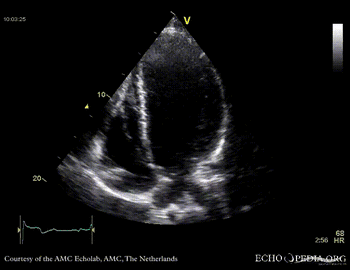

Case 10